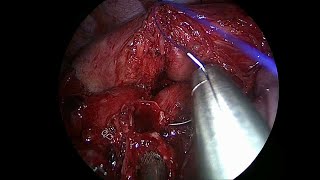

Useful tricks to divide the upper lobe bronchus through uniportal VATS video

Useful tricks to divide the upper lobe bronchus through uniportal VATS

Useful tricks to divide the upper lobe bronchus through uniportal VATS Tricks to transect the upper lobe vein through uniportal VATS

Useful tricks to divide the upper lobe bronchus through uniportal VATS

Useful tricks to divide the upper lobe bronchus through uniportal VATS Tricks to transect the upper lobe vein through uniportal VATS